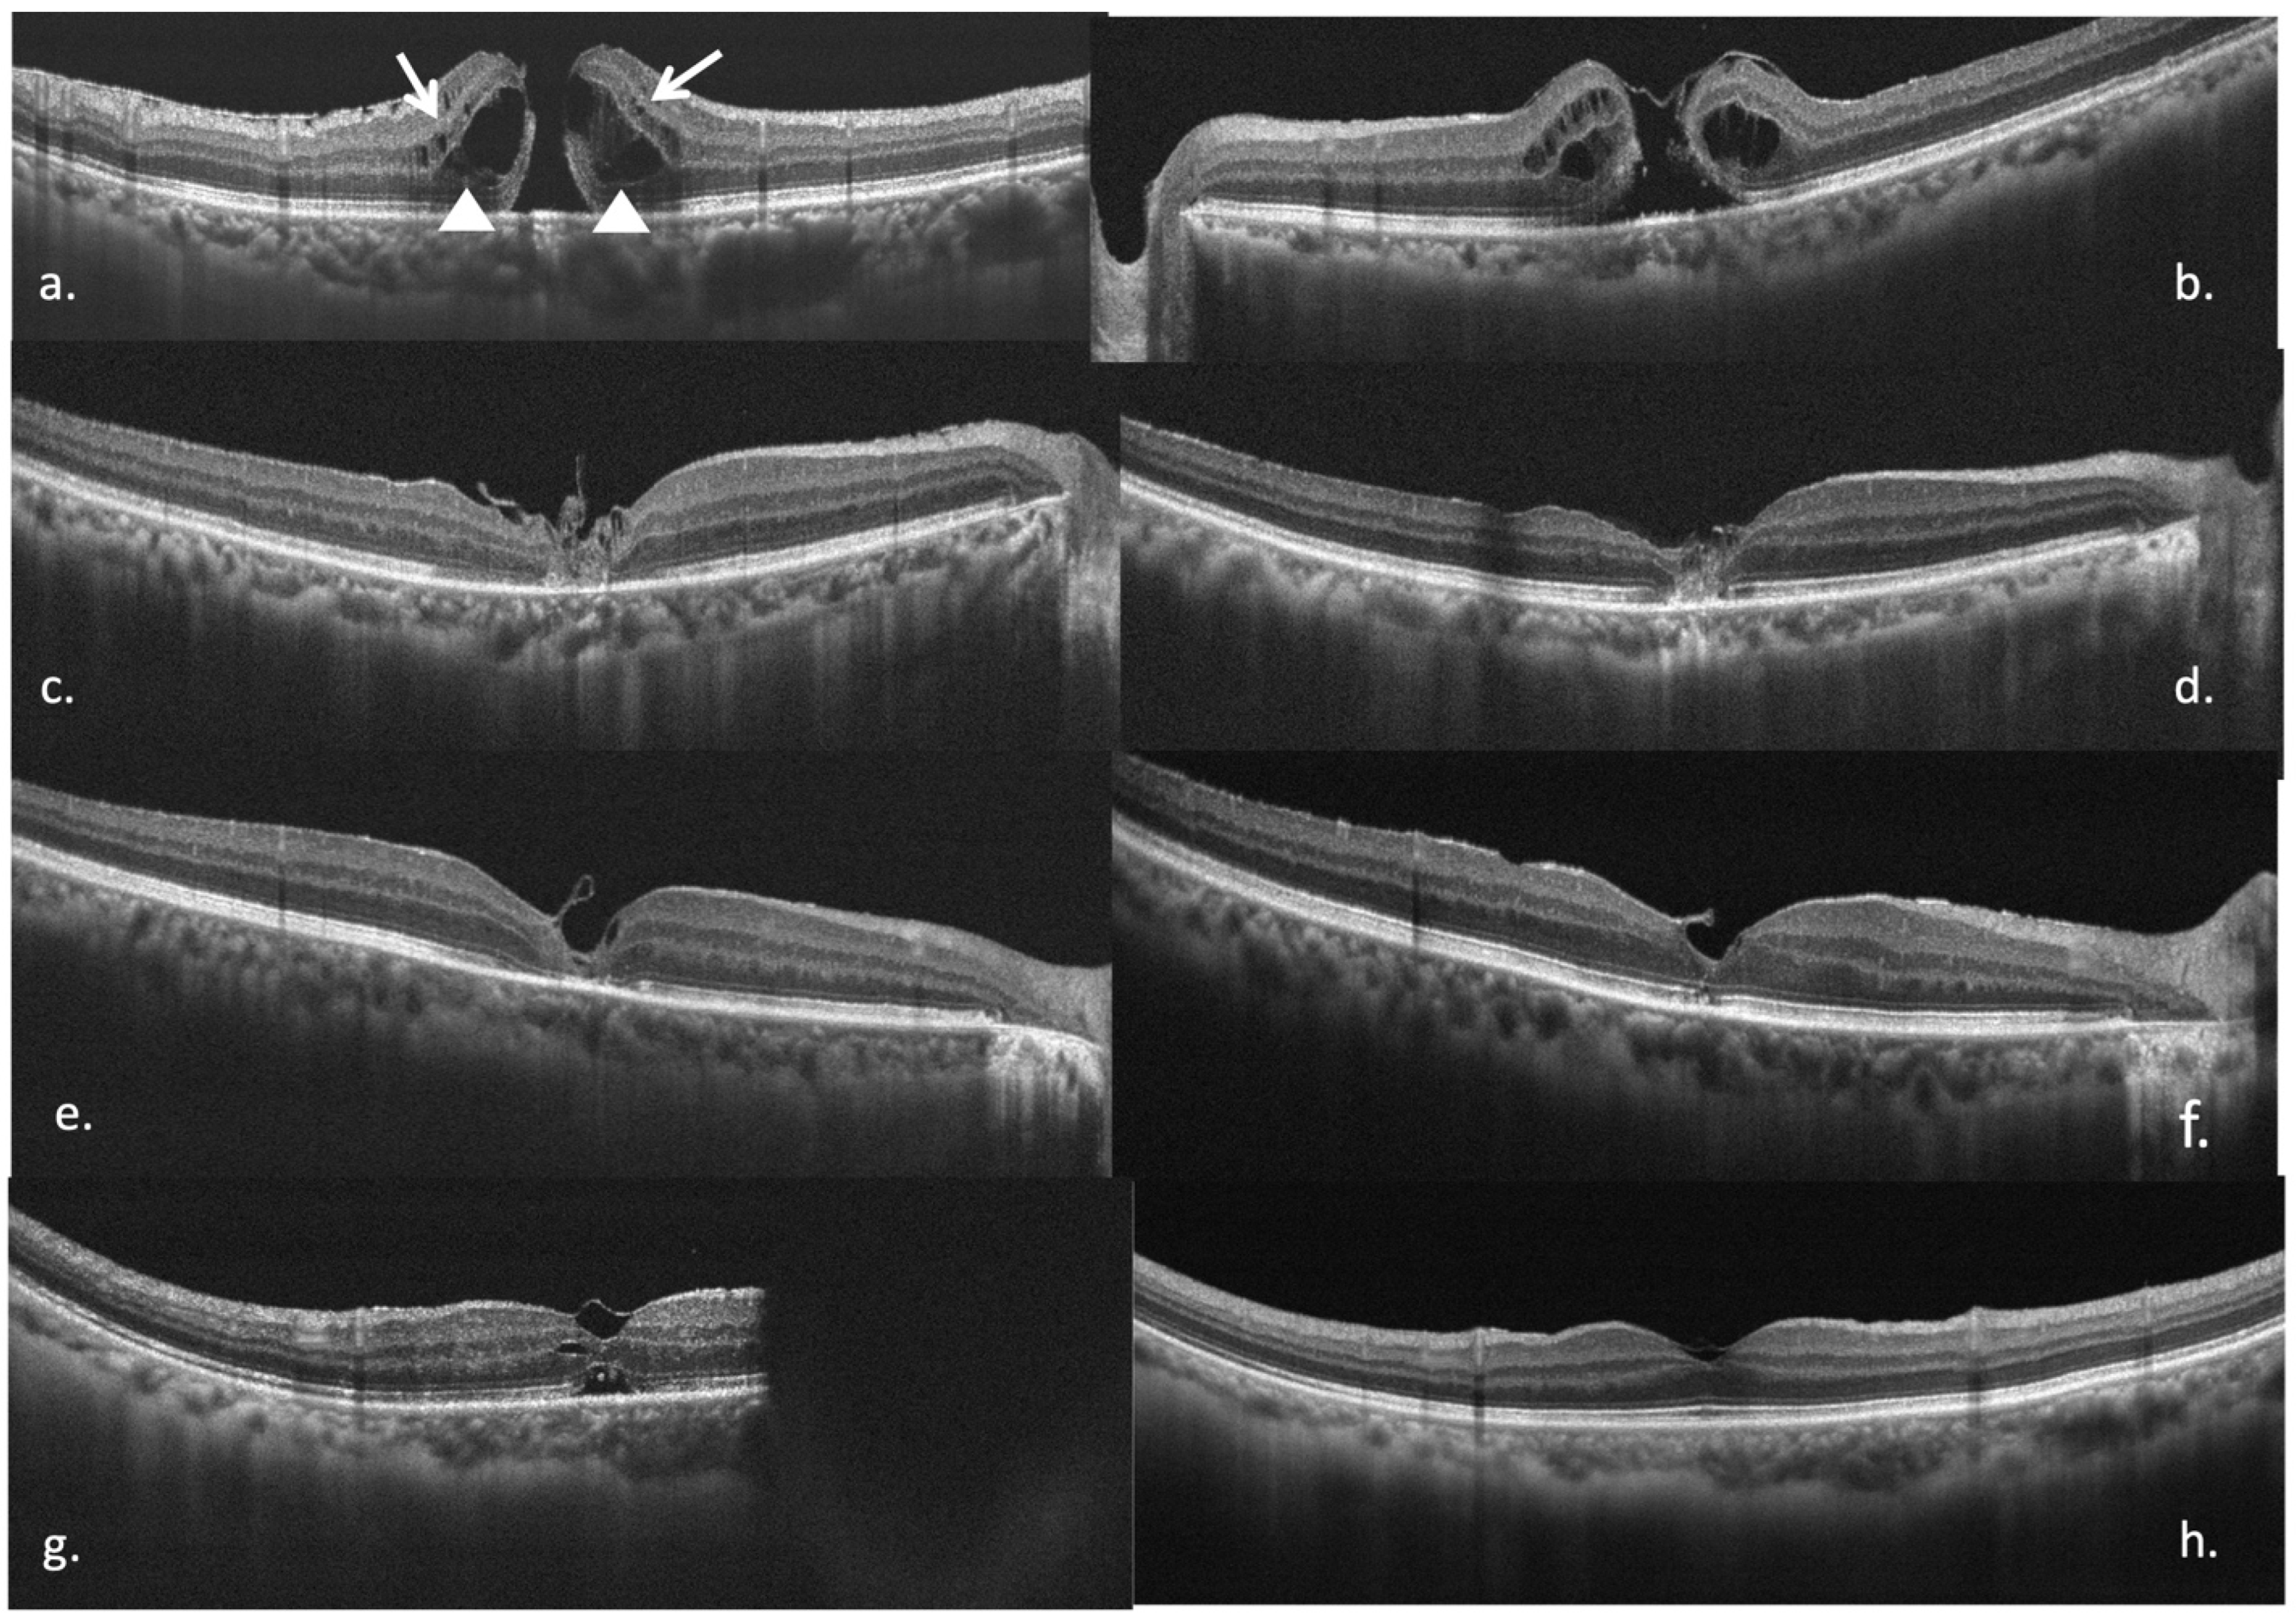

3.4. Secondary Outcomes: Micro-Structural Recovery